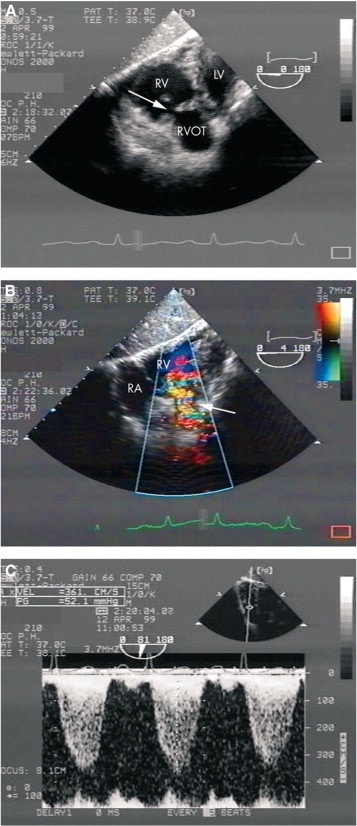

- History of carcinoid heart disease with previous tricuspid replacement

- Progressive pulmonary stenosis and shortness of breath

- TTE shown 1 day prior to pulmonary valve replacement

- Severe PS with max velocity 4.6m/s and mean gradient 84.6mmHg

- Moderate PR

- Mod-Severe RV dysfunction

- Carcinoid involvement of pulmonic valve classically showed thickened valve with restricted motion